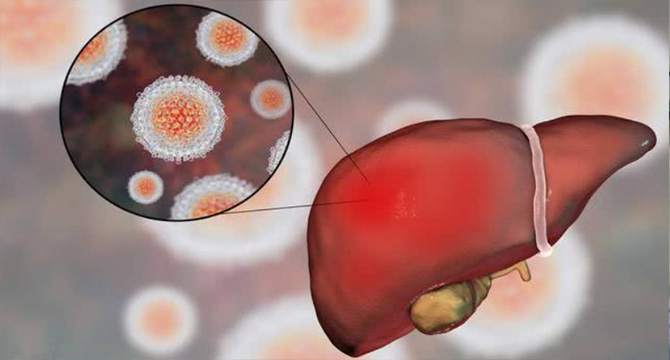

本着“传承中医药文化,弘扬国粹精髓”的宗旨和以人类健康事业追求永无止境为己任,秉承“为天地立心,为生民立命,为经圣继绝学,为万世开太平”之信念,峨眉山壹康棠中医馆以中医药传承创新为核心,充分利用峨眉仙家修真炼气、养生健身和丰富的中草药资源,一心一意造福广大肝病患者。

为延续廖氏祖传秘方验方和仙草奇药,让旷世奇方得以更好的传承,造福世人,服务百姓,特选址峨眉院子开设壹康棠中医馆,由专业执业中医师长期坐堂就诊。医馆恪守“炮制虽繁必不敢省人工,品味虽贵必不敢减物力”之古训,用各种名贵的中药材配制成组方,达到从根本上治疗的目的。